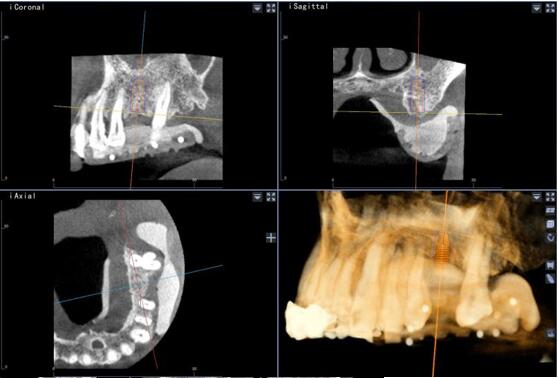

術(shù)前種植體規(guī)劃

術(shù)中實(shí)時(shí)導(dǎo)航

術(shù)中實(shí)時(shí)種植導(dǎo)航

術(shù)后精度驗(yàn)證

種植體類 型植入點(diǎn) 末 端角 度

26 計(jì)劃<->實(shí)際 0.88 0.96 2.68